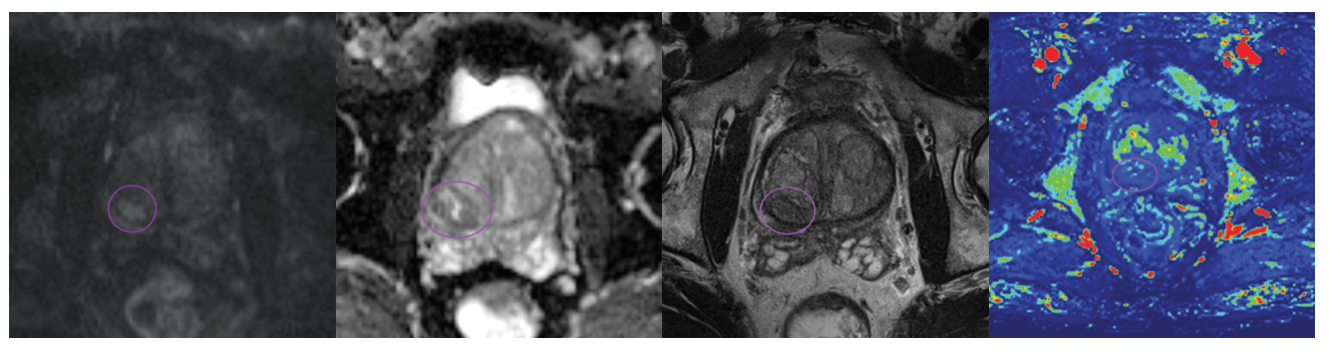

Đánh giá PI-RADS 3 . Phiên bản mới 2.1 (2023)

Các tổn thương này được phát hiện trên cộng hưởng từ (MRI) bằng cách sử dụng kết hợp các trình tự T2I , DWI/ADC và DCE.